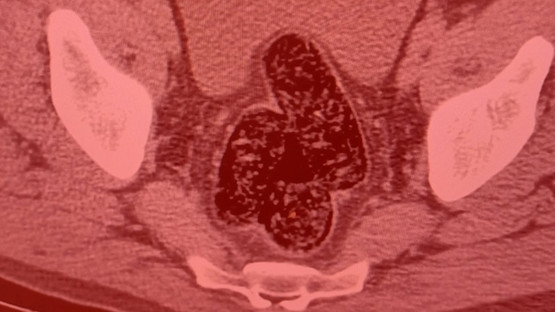

Yapılan aramalar sonucunda, şahsın pantolonunun cep kısmında iki parça halinde şeffaf poşete sarılı vaziyette 10.17 gram gelen metamfetamin maddesi ele geçirildi. Şahsın devam eden işlemlerinde gözlerindeki kızarıklık, yemek ihtiyacı istememesi, aşırı tedirgin davranışlar sergilemesi üzerine yapılan iç beden muayenesi neticesinde röntgen vasıtasıyla makat ve bağırsak kısmında uyuşturucu kapsülleri olduğu tespit edildi.

Doğal yöntemlerle şahıstan 12 adet kapsül toplam daralı ağırlığı 345.19 gram gelen metamfetamin ele geçirildi. Şahsın üzerinden ve iç bedeninden toplamda 355.36 gram uyuşturucu madde ele geçirildi.